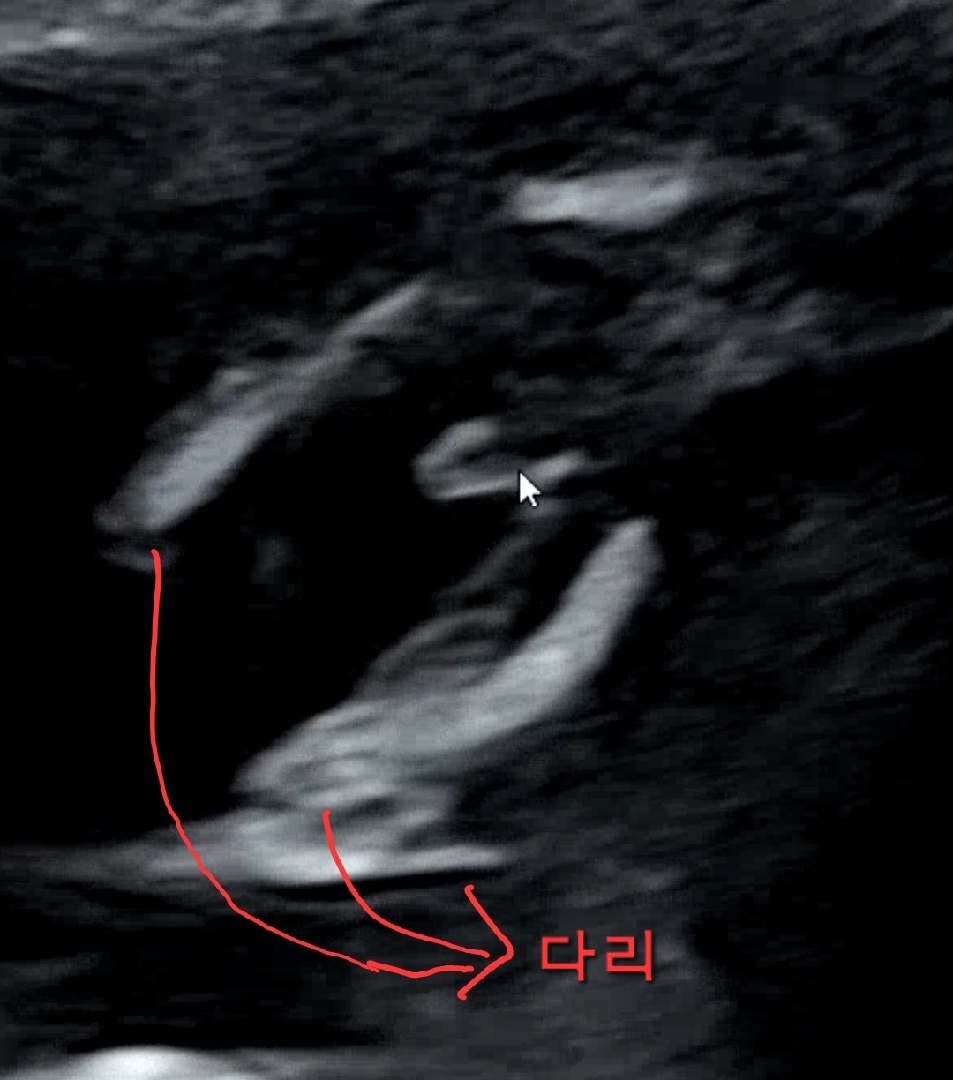

14주차 초음파로 성별 거의 99프로 확정..!

다리 사이에 자기주장 강한 어떤 것이 떡하니 있더라구요! 아마 99프로 남자인듯해요 크크 와이프는 벌써 남자아이 엄마되는 걱정중😂